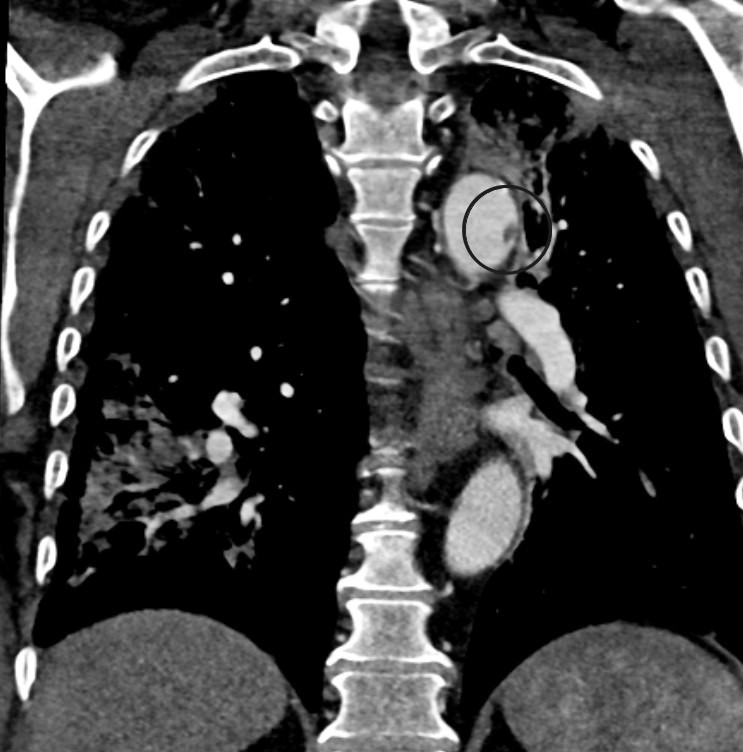

Postoperatively, all symptoms in the lower extremities improved, but the patient's oxygen saturation was noticeably low with SpO2 of 94.5 % (reference range > 99 %). Blood gas analysis while the patient was receiving 3 L O2 via nasal catheter showed pH 7.47 (7.36−7.44), pCO2 4.5 kPa (4.5−6.1) and pO2 8.9 kPa (> 9.6). CT angiography of the thoracic aorta was performed, which revealed several pulmonary emboli in both lower lobes as well as ground-glass opacities typical of previous COVID-19 pneumonia (Figure 2). In addition, a 7 mm pendulating thrombus was seen in the distal aortic arch (Figure 3). Dalteparin was increased to 10 000 IU × 2, and the patient received non-invasive respiratory support in the intensive care unit.